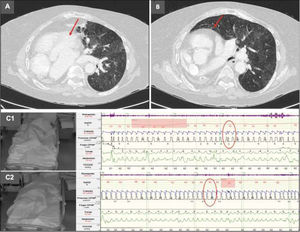

This is the case of a 80-year-old woman with a past medical history of congenital pulmonary hypoplasia, dextrocardia and bronchiectasis (Fig. 1A and B), severe pulmonary hypertension, and severe mixed ventilatory failure. Six years ago, she initiated home noninvasive ventilation (NIV) for chronic hypercapnia and nocturnal hypoventilation. Optimal compliance and adherence were achieved through telemedicine [1,2]. Over the past year, the patient had multiple hospital admissions for non-infectious respiratory and cardiac decompensation, with an increase in his baseline hypercapnia (67mmHg) and hypoxemia. Despite various adjustments to her ventilatory parameters during several visits, including an increase in nocturnal O2 to 2L [3,4], there was no improvement in hypercapnia and respiratory failure. We decided to perform a nocturnal polysomnography with manual titration of NIV and transcutaneous capnography, which showed a baseline O2 saturation of 86–88%, asynchronies, flow limitation and positional snoring in the left lateral decubitus position. When the patient was changed to the right lateral decubitus position, the obstructive events and hypoventilation improved significantly with an increase in oxygen to 3L/min (Fig. 1C). These findings demonstrated a positional component associated with the patient's underlying congenital pathology, leading to sleep-related hypoventilation. Daytime blood gas analysis revealed a marked reduction in hypercapnia after hypoxemia was corrected. Postural interventions and continued use of her NIV were recommended.

(A) Chest computed tomography demonstrating congenital dextrocardia (arrow). (B) Congenital pulmonary hypoplasia (arrow). (C1) NIV titration in the left lateral decubitus position showing ventilatory asynchronies and hypocapnia (oval). (C2) NIV titration in the right lateral decubitus position with resolution of asynchronies and improved oxygen saturation (oval).